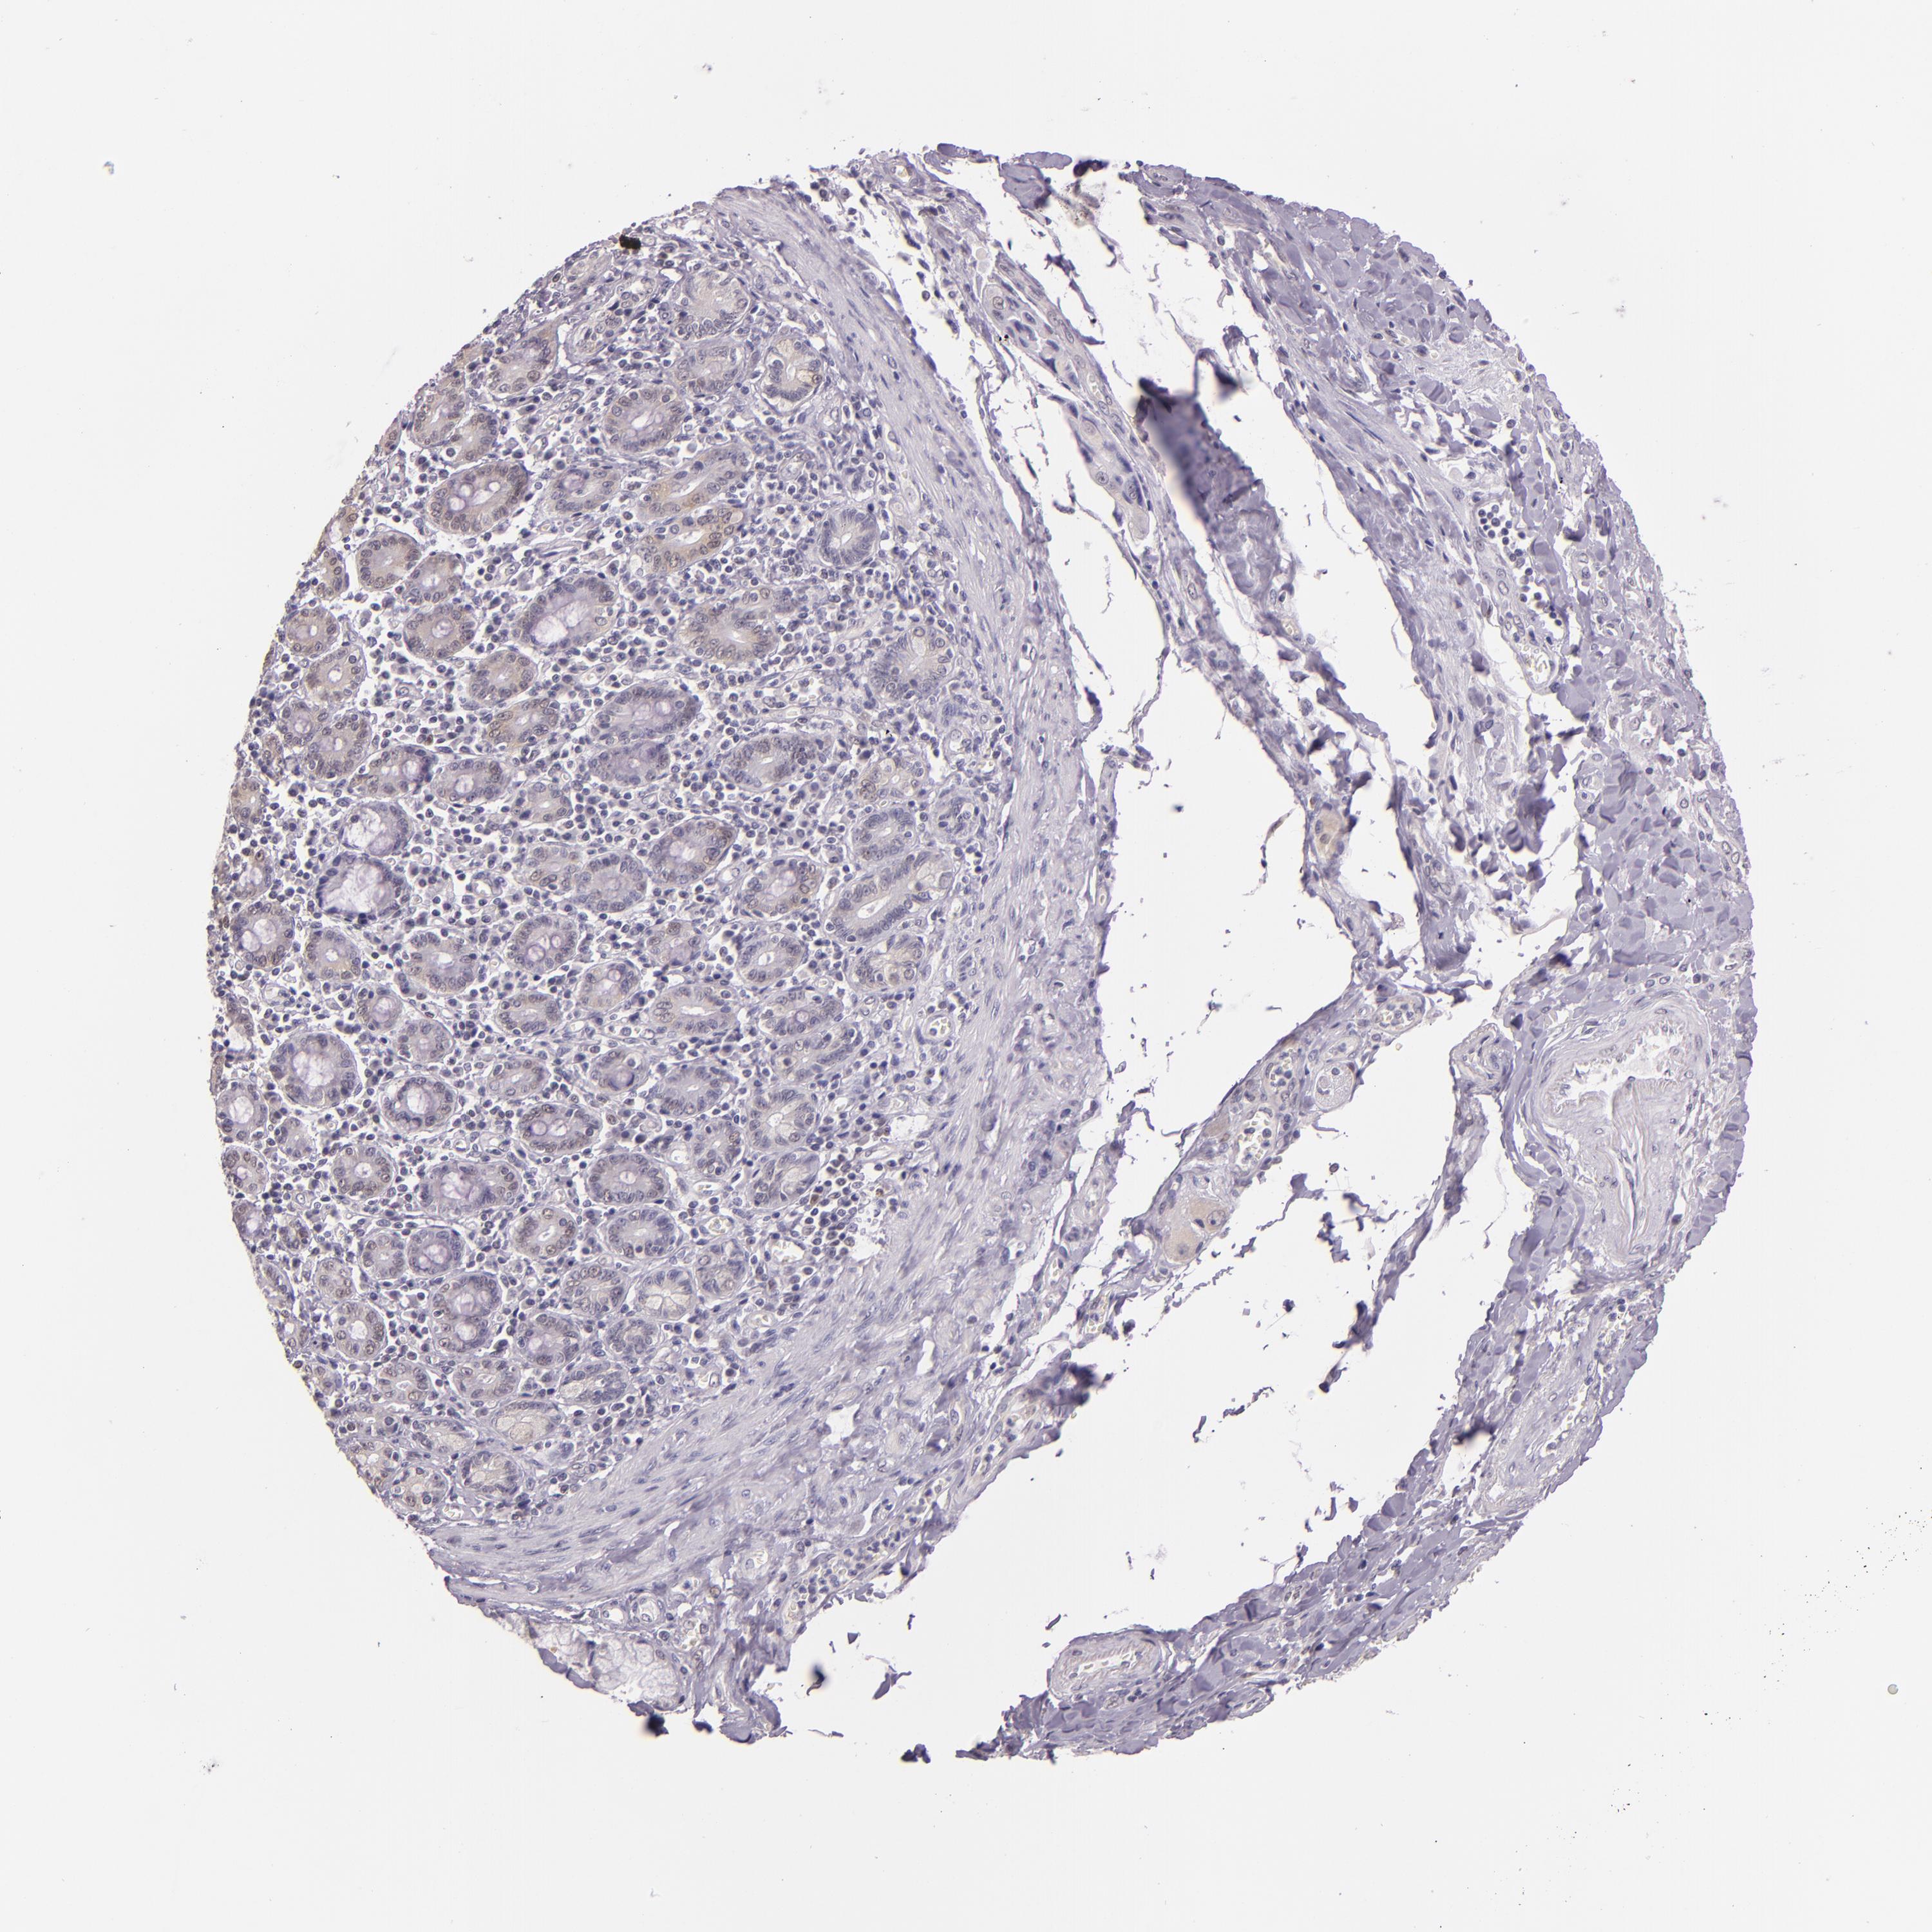

PANCREATIC CANCER - Protein expressioni

A mouse-over function shows sample information and annotation data. Click on an image to view it in a full screen mode. Samples can be filtered based on level of antibody staining by selecting one or several of the following categories: high, medium, low and not detected. The assay and annotation is described here.

Note that samples used for immunohistochemistry by the Human Protein Atlas do not correspond to samples in the TCGA dataset.

Antibody stainingi

Antibody staining in the annotated cell types in the current human tissue is reported as not detected, low, medium, or high, based on conventional immunohistochemistry profiling in selected tissues. This score is based on the combination of the staining intensity and fraction of stained cells.

Each image is clickable and will lead to virtual microscopy that enables deeper exploration of all samples and also displays staining intensity scores, fraction scores and subcellular localization as well as patient and tissue information for each sample.

Antibody HPA052504

Antibody CAB002056

Staining

High

Medium

Low

Not detected

Intensity

Strong

Moderate

Weak

Negative

Quantity

>75%

75%-25%

<25%

None

Location

Nuclear

Cytoplasmic/membranous

Cytoplasmic/membranous,nuclear

Adenocarcinoma, NOS